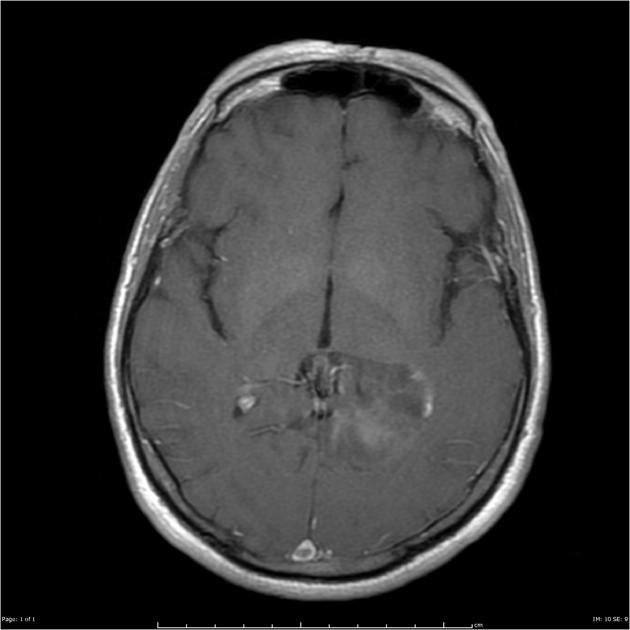

AA T1 with gad

GBM T1 with gad

The treatment fields for HGG in pediatrics, similar to adults is the imaging enhanced region plus a margin. The initial GTV is the MRI T2 abnormality (edema). The initial CTV = GTV + 1.5 cm, corrected for anatomical barriers. The usual dose to this volume is 50.4 - 54 Gy at 1.8 Gy/fraction. The second GTV (boost GTV) is the T1+gadolinium enhancement. The second CTV=GTV+1 cm. This is then carried to 59.4 Gy.

• The final GTV = T1+ gad image

• The final CTV = GTV (final) + 1 cm margin (⇒ to 59.4 Gy)